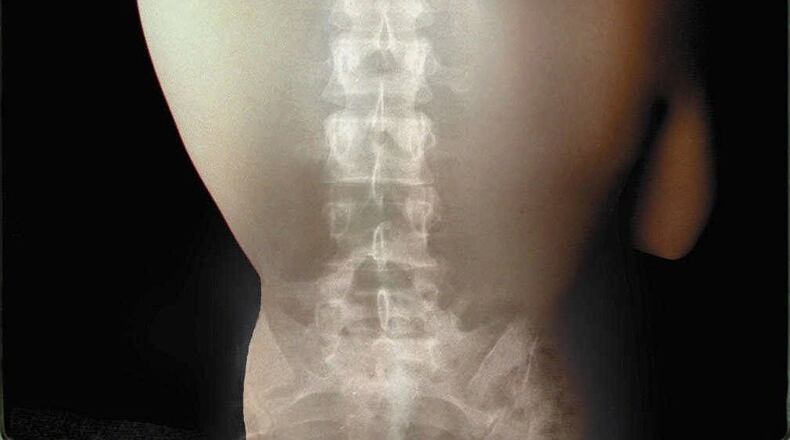

Osteoporosis is typically found during a screening, specifically a DEXA scan (dual-energy X-ray absorptiometry). Used to measure bone density, a DEXA scan every two years is recommended for women 65 years old or older, and for men 70 and older.